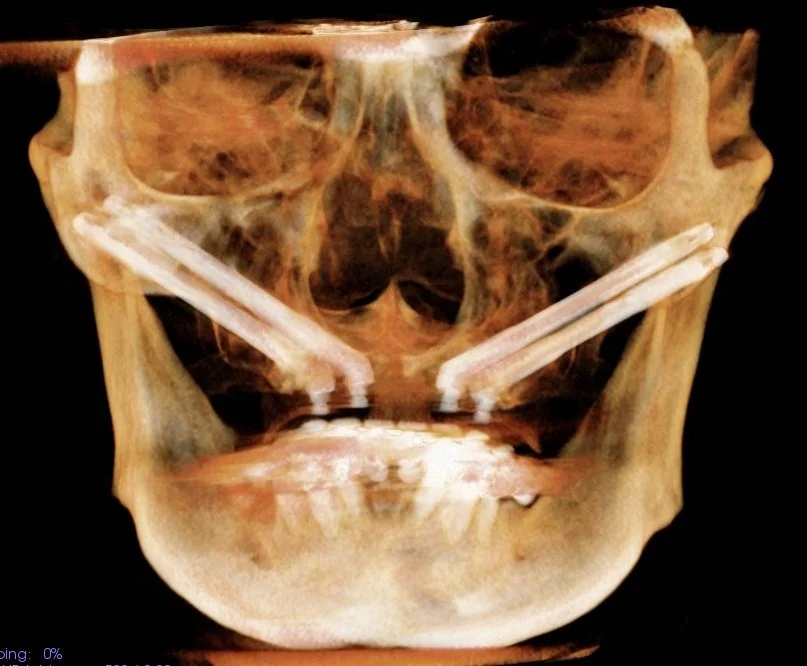

Zigomatik İmplantlar

• Zigomatik implantlar üst çenede arka bölgede kemik erimesine ek ön bölgede de kemik erimesi olduğu durumlarda üst çene kemiğinde hiç kemik kalmadığı durumlarda uygulanan implantlardır.

• Elmacık kemikleri olrak da adlandırılan zigoma kemiklerine uygulanan, normal implantlardan çok daha zun implantlardır.